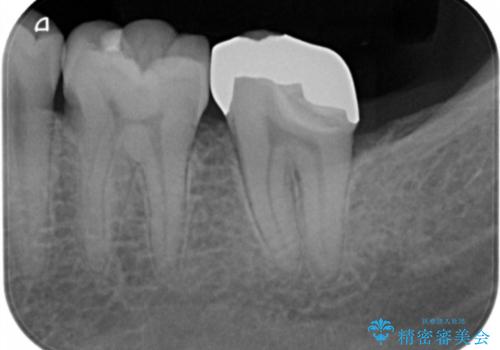

二つの提案をしたところ、①を選択されたのでゴールドインレーによる治療を行いました。

- ゴールドインレー 11万円費用は治療当時の料金となります

ゴールドインレーは歯質との適合がよく

虫歯の再発リスクや割れるというリスクが低いです。